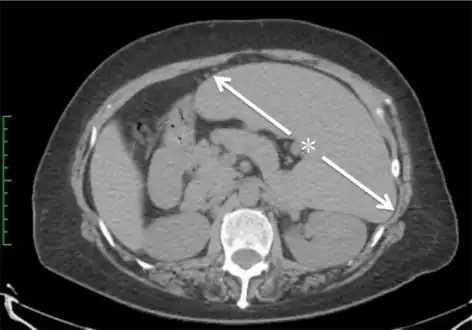

Abdominal CT is the most accurate and spleen need to be larger 2-3 times to be palpable below the costal margin in physical examination that can help in diagnosis.

Computed tomography shows a massively enlarged spleen ( splenomegaly).